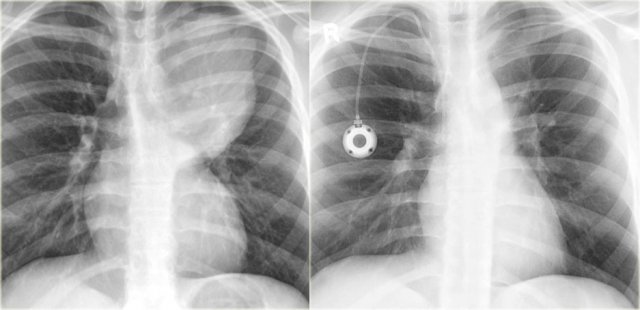

Treatment for Ewing's sarcoma includes surgery, radiation and chemotherapy.

On the left a Ewing sarcoma, presenting as a large pleural soft tissue mass (same case as above).

On the right, the soft tissue mass has completely resolved after neoadjuvant chemotherapy.